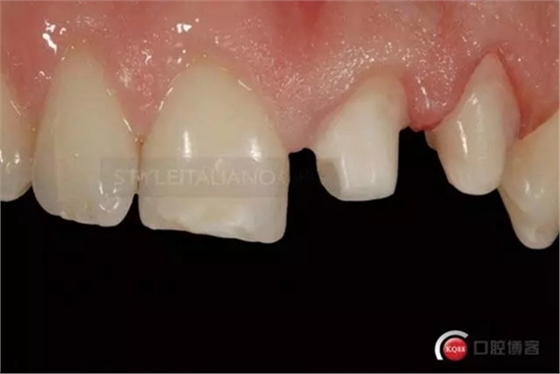

This is Italo, 32 years old, a few hours after a bicycle accident, coming from the hospital emergency room, on February 2006

The patient has a pulp hemorrhage on tooth 2.1 suffering for a deep palatal fracture